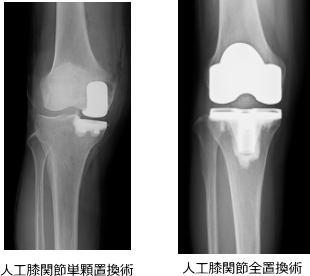

関節鏡手術/骨切り術/人工膝関節置換術から選択します。

人工膝関節置換術は、変形した関節表面を人工関節(インプラント)に置き換える方法で、痛みの軽減が期待できます。

- 単顆置換術(UKA):内側または外側の限局した変形に対して、痛んだ側のみを置換

- 全置換術(TKA):関節全体の高度変形に対して、膝全体を置換